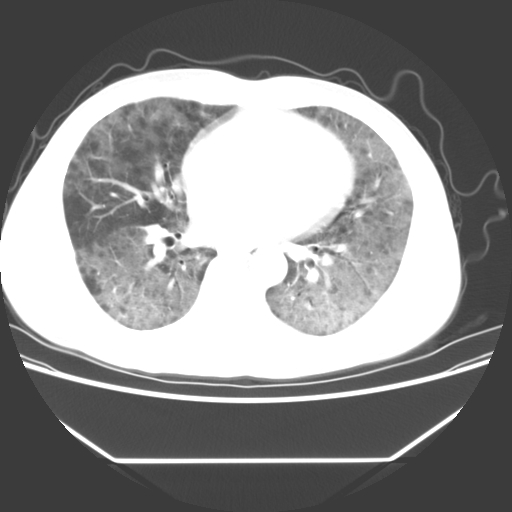

病人55岁,咳嗽,胸闷

忘了传病史了,病人55岁,咳嗽,胸闷

两肺部呈“毛玻璃”状改变,原因待查考虑感染性病变

病人是否发烧,两肺“磨玻璃”影,其间见空气支气管征和碎路石征。考虑肺泡蛋白沉着症。

两肺广泛对称磨玻璃样影,密度不均,考虑机遇性肺部感染。

双肺弥漫磨玻璃样病变,病史很重要。有感冒或发烧史,甲流不除外。无发烧可考虑肺泡蛋白沉积,但肺泡蛋白沉积边缘往往较清晰,与正常肺组织分界清晰

两肺弥漫间质性病变,考虑肺泡蛋白沉着症。建议进一步检查。